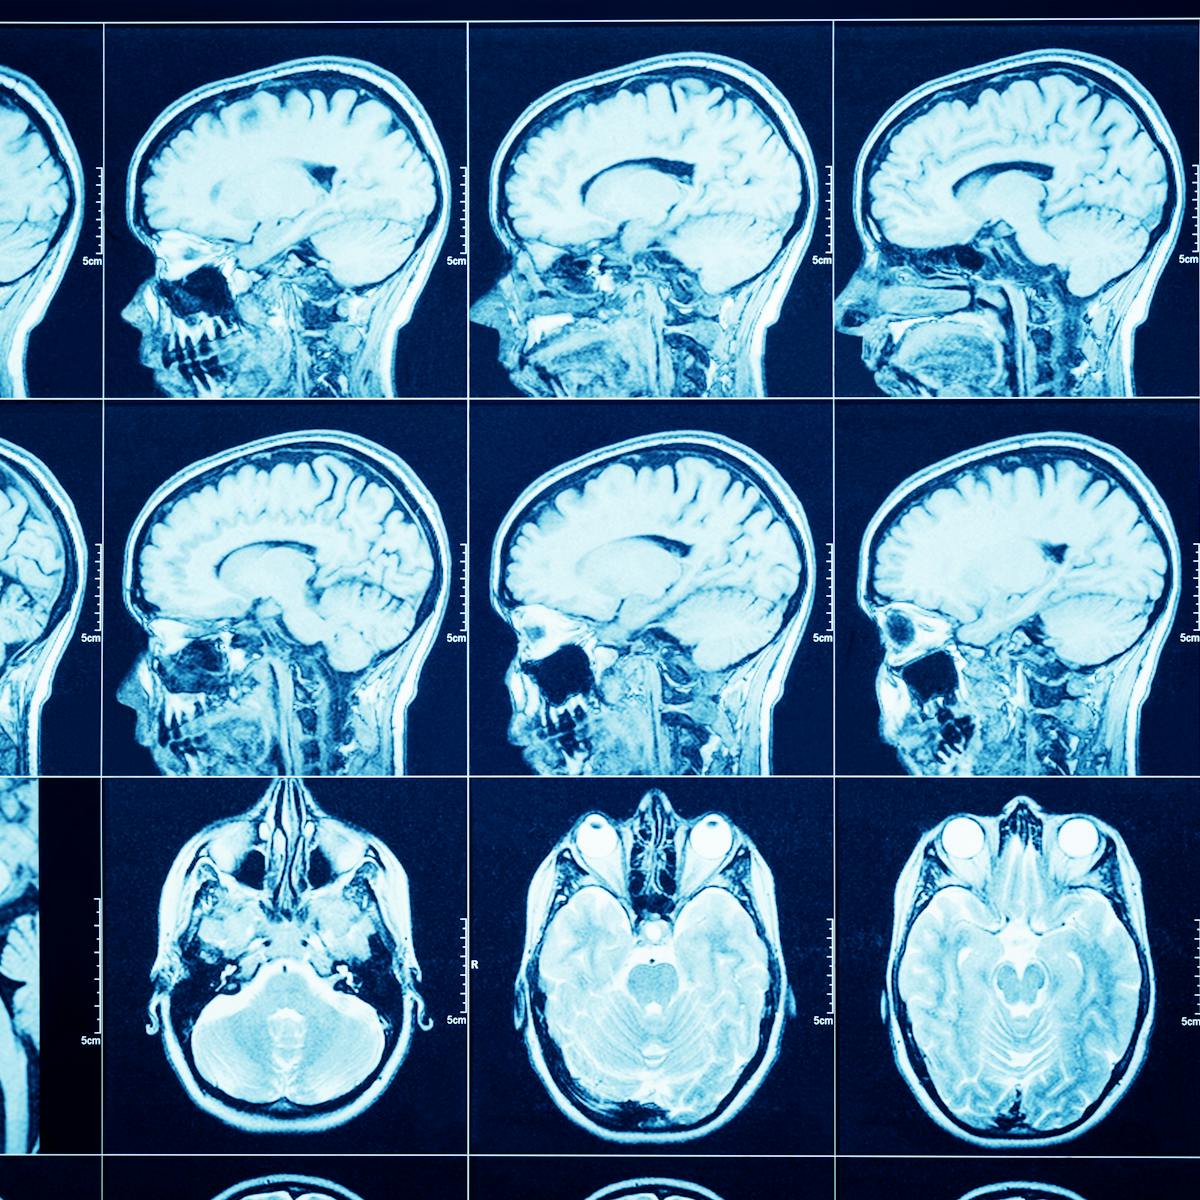

A ct scan confirmed he. As many as 1 in 3 patients recovering from covid 19 could experience neurological or psychological after effects of their infections experts told stat reflecting a growing consensus that the. Global united states cluster headache syndrome drug market research with covid 19 after effects development factors and growth analysis 2020 2026 published.